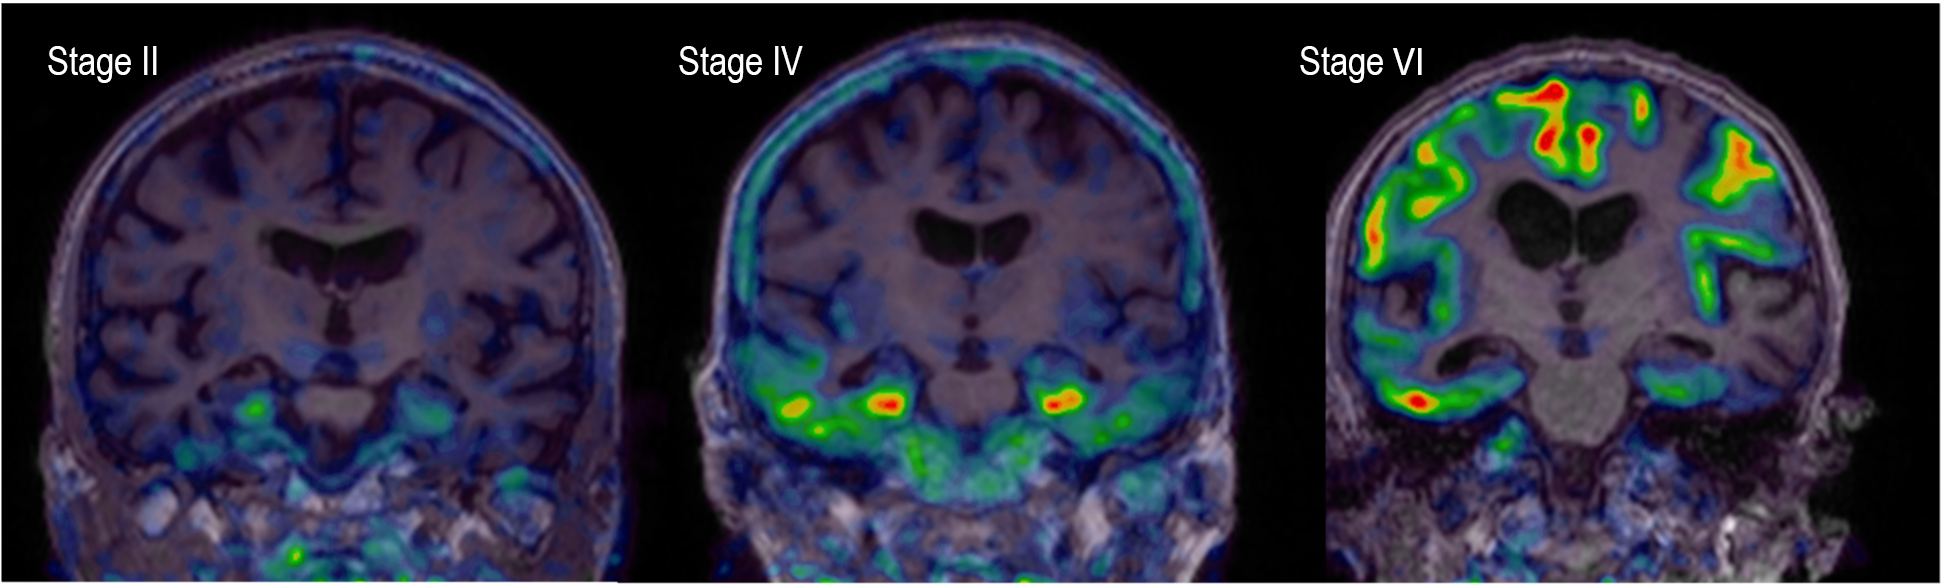

Until a decade ago, a definite diagnosis of Alzheimer’s disease (AD) could only be made after autopsy and confirmation of amyloid and tau pathology in the brain. Neurologists could only give the diagnosis of probable AD to patients with dementia. The absence of biomarkers to confirm the biological diagnosis made it impossible to diagnose AD early, prior to dementia. The Louvain Aging Brain Lab has been among the first in Europe to describe the spatio-temporal progression of Alzheimer’s pathology in living humans, using specific radiotracers and positron emission tomography to detect amyloid and tau deposits in the brain. We have “brought to life” neuropathological classifications, obtained at post-mortem, by transposing them into brain imaging classifications, applicable to detect Alzheimer’s pathology before the onset of symptoms. It appeared that amyloid PET was able to predict which patient would progress to dementia six years later with an overall predictive value of 87%. However, regional amyloid did not predict well the specific cognitive deficits, and up to 20% of cognitively normal older adults do have amyloid pathology in their brain. In contrast, tau PET images (see figure) are much more closely associated to brain dysfunction and cognitive deficits. We are currently developing new ways of assessing subtle cognitive loss, including spatial navigation or linguistic abilities, in apparently normal older adults. This work is of particular importance in the context of upcoming therapeutic trials aiming at preventing the onset of AD in non-demented individuals with evidence of Alzheimer’s pathology. The recent development of blood tests targeting amyloid and tau, of cognitive tests available on smartphone apps, and the large amounts of data collected using brain imaging all require artificial intelligence tool to be analyzed optimally.

Tau PET images in patients with different levels of Alzheimer’s pathology

Early stages (I-II) are commonly observed in older individuals, even without memory impairment. Stages III-IV are most often associated with mild cognitive impairment and late stages (V-VI) with dementia.